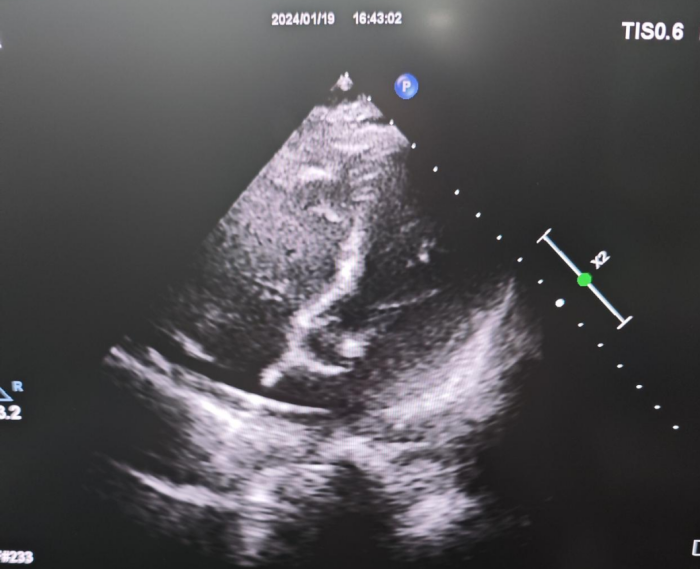

导丝通过PFO进入左房